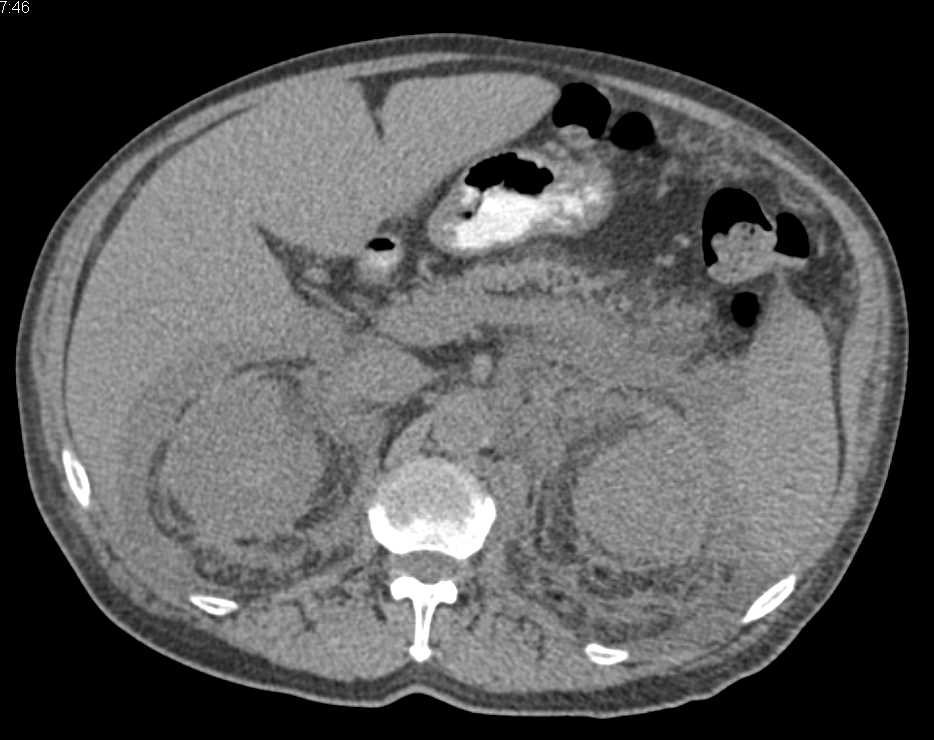

Transitional Cell Carcinoma Left Ureter